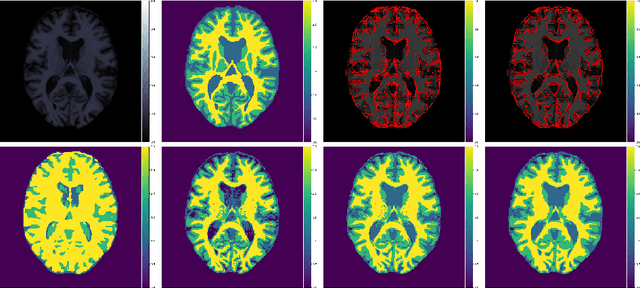

Abstract:In a broad range of fields it may be desirable to reuse a supervised classification algorithm and apply it to a new data set. However, generalization of such an algorithm and thus achieving a similar classification performance is only possible when the training data used to build the algorithm is similar to new unseen data one wishes to apply it to. It is often unknown in advance how an algorithm will perform on new unseen data, being a crucial reason for not deploying an algorithm at all. Therefore, tools are needed to measure the similarity of data sets. In this paper, we propose the Data Representativeness Criterion (DRC) to determine how representative a training data set is of a new unseen data set. We present a proof of principle, to see whether the DRC can quantify the similarity of data sets and whether the DRC relates to the performance of a supervised classification algorithm. We compared a number of magnetic resonance imaging (MRI) data sets, ranging from subtle to severe difference is acquisition parameters. Results indicate that, based on the similarity of data sets, the DRC is able to give an indication as to when the performance of a supervised classifier decreases. The strictness of the DRC can be set by the user, depending on what one considers to be an acceptable underperformance.

Abstract:Suppose one is faced with the challenge of tissue segmentation in MR images, without annotators at their center to provide labeled training data. One option is to go to another medical center for a trained classifier. Sadly, tissue classifiers do not generalize well across centers due to voxel intensity shifts caused by center-specific acquisition protocols. However, certain aspects of segmentations, such as spatial smoothness, remain relatively consistent and can be learned separately. Here we present a smoothness prior that is fit to segmentations produced at another medical center. This informative prior is presented to an unsupervised Bayesian model. The model clusters the voxel intensities, such that it produces segmentations that are similarly smooth to those of the other medical center. In addition, the unsupervised Bayesian model is extended to a semi-supervised variant, which needs no visual interpretation of clusters into tissues.